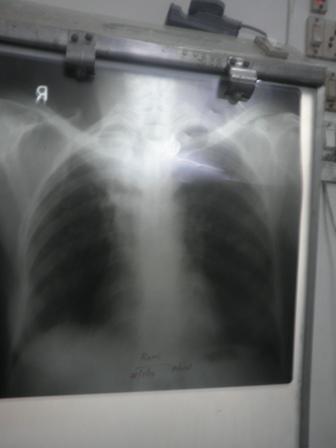

rani before treamtnent

rani after treament of 3 months